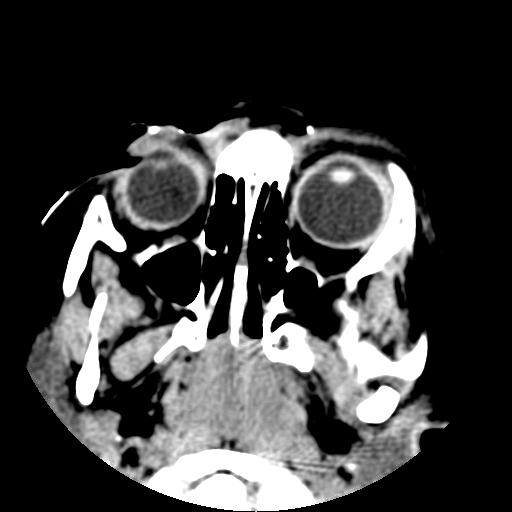

以下是引用深泽交通医院在2009-10-16 8:25:00的发言:[br]右眼环出血伴异物

以下是引用卜一在2009-10-16 15:01:00的发言:[br]右眼球挫裂伤伴异物!

以下是引用拾荒者在2009-10-17 18:38:00的发言:[br]鼻面部皮下积气,右侧睑缘及眼球壁高密度异物影,左侧眼球壁晶状体内侧缘处是圆形低密度影。低密度异物?应提请眼科医生注意。